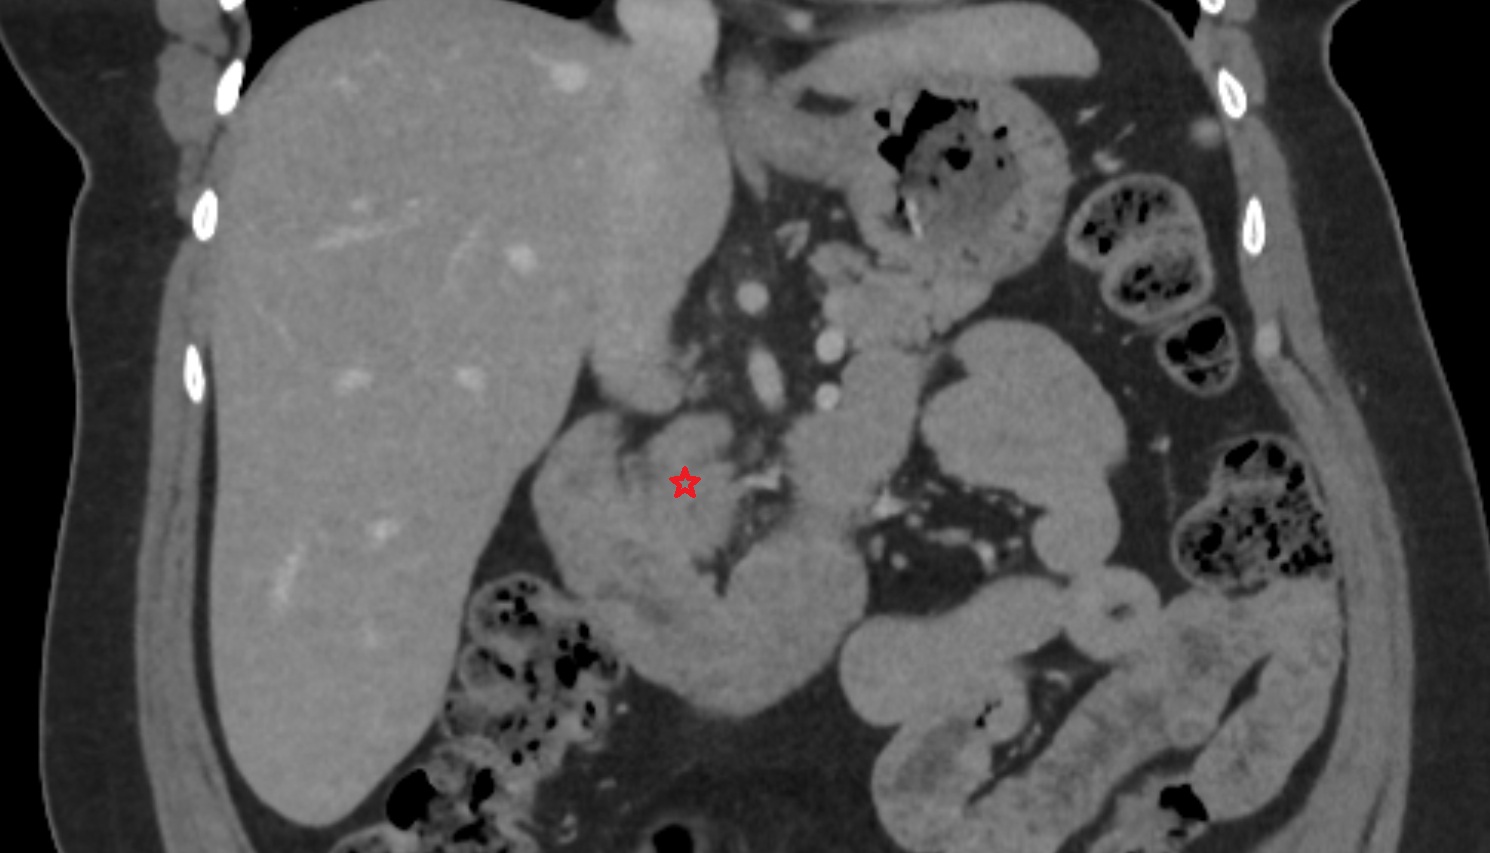

- kidneys

- Right kidney

- Left kidney

- Kidney cortex (Renal cortex)

- Renal medulla

- Renal pyramids

- Renal fascia

- Renal artery

- Renal vein

- Left renal vein

- Right renal vein